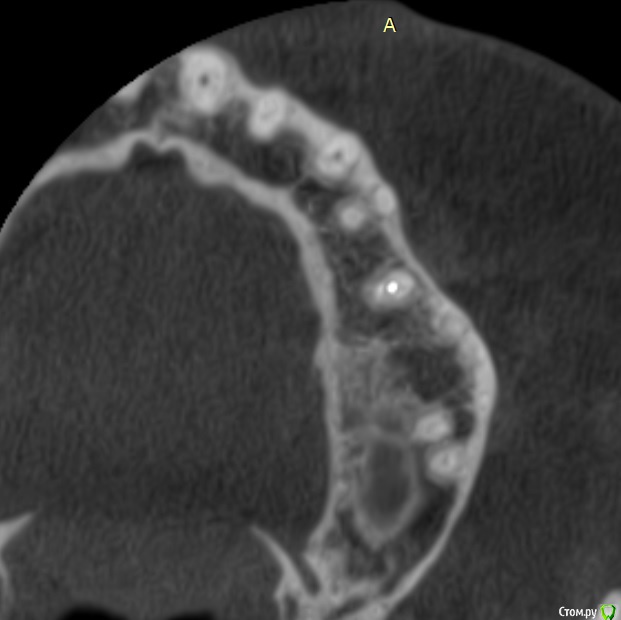

Ker Опубликовано 15 сентября, 2016 Поделиться Опубликовано 15 сентября, 2016 (изменено) Да простят меня терапевты, мне не нравится ваш зуб... разрушение ниже уровня десны, контактный пункт не создан..Дистально уступ получился, похоже что матрицу недотянули до края зуба, плюс еще стоит посмотреть насчет второго канала. Недопломбировка есть однозначно, хоть и небольшая, канал открывается прямо на рентген апексе. Само не пройдёт. Изменено 15 сентября, 2016 пользователем Ker Ссылка на комментарий

Verasss Опубликовано 28 сентября, 2016 Автор Поделиться Опубликовано 28 сентября, 2016 эх, ну два врача мне зуб делали. один нерв вынимал, второй пломбировал, так уж вышло. и снимки там разных проекций и КТ есть. Дело не в этом. Когда оставила зуб в покое, жизнь постепенно наладилась, но вернулась с дождями-холодами числа 22.09.Уже и бегала к хирургу, показаний для разреза нет, отека нет. По КТ вроде в гайморовой то ли киста то ли полипы. Гноя, насморка нет. Болит и она периодически.Но больше беспокоит, что ноет десна и ощущение мягкости, ноет не в карманах, а в где-то в верхушке корня что ли. Если сильно втянуть воздух, то как бы весь зуб ощущается в этом периодонте и отдает в гайморову. И 6-ка тоже стала немного чувствительной перкусии.На холод-тепло сам зуб не реагирует, сам зуб вообще не беспокоит, только ткани вокруг него.А как болит канал мне показали, дунув хорошенько воздухом в стоматологии на 6-ку рядом (там пломба близко к нерву), и вот это не такая боль. А вообще, день на день не приходится. То гайморова беспокоит, до десна, то всё вместе, то почти ничего. Основные раздражители: механические (например, тряска в маршрутке, трогание зуба языком, чистка зубной нитью, твердая пища), дожди-холода, психологические (тревога, стресс). Причем в один день зуб может не беспокоить, ткани ощущаться твердыми, а в другой разныться. КТ прилагаю архивом от 08.09. К сожалению, чтобы нарезать фотки, мне нужно переустанавливать память с бОльшей мощностью, а такой возможности у меня пока нет. Надеюсь, кто-нибудь посмотрит). https://yadi.sk/d/5Zw3pMFevs7Hd Делать снимки свежие уже боюсь, уже много чего наделано, и на визиографе, и простых рентгенов, и КТ. В общей сложности где-то +10. Ещё и лоры требуют, чтоб я делала КТ пазух с их точки зрения, а государственный - чтоб вообще рентген сделала в поликлинике. В общем, засада. Хочется какой-то универсальный сделать. Может, физио поделать? Т.е. у меня как пациента по-прежнему 2 варианта: или острое воспаление, которое не видит КТ от недопломбировки верхушки или занесения чего-либо, а гноя нет, может, иммунитет хилый, свищ не делает, а если вскрыть зуб, то пойдет? был отек губы и немного щеки как-то после очередных постукиваний у стоматолога, но я выпила антибиотик, и на следующий день прошло. (плюс я антибиотики пропила курсом и анальгин иногда); и вообще воспаления у меня всегда так проходят сразу в хронической форме, долго и мутно, без горячки и адовых болей. (Хотя....если можно как-то сравнить с ногой, например, в прошлом году, то там был гнойник с опуханием всей стопы, всё как в учебнике...) Или это сильная травма зуба и периодонта при пломбировке горячей гутапперчей, усиленная моими походами к стоматологам и постукиванием там по оному. Гайморова присоединилась не сразу, а где-то недели через 2 после пломбировки. Т.е. как-то мне видится, что врачи правы,и там не гайморит, а была уже большая киста или полипы, которую эта агрессивная пломбировка потревожила. Спасибо!Если кто ответит, и на том спасибо). Ссылка на комментарий

Verasss Опубликовано 28 октября, 2016 Автор Поделиться Опубликовано 28 октября, 2016 еще снимки Ссылка на комментарий

Verasss Опубликовано 28 октября, 2016 Автор Поделиться Опубликовано 28 октября, 2016 и еще Ссылка на комментарий

Verasss Опубликовано 23 ноября, 2016 Автор Поделиться Опубликовано 23 ноября, 2016 Сделала ещё 1 кт, спустя почти 2,5 месяца после первого. Посмотрите, пожалуйста, есть ли изменения? Напомню, что пункцию гайморовой мне сделали. Ссылка на комментарий